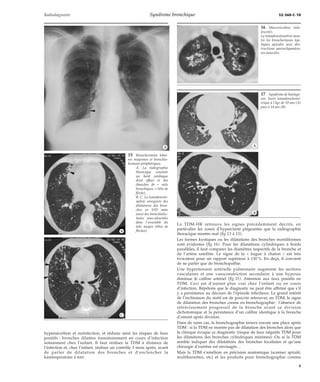

11 Artère et bronche : les

« jumelles ».

a. OEil vasculaire ; b. oeil

bronchique ; c. image en

« pain à cacheter » ;

d. image en « anneau » ;

e. « bague à chaton ».

12 Bronchectasies kysti-ques.

Les sacs, kystes en diver-ticules

bronchiques présentent

des niveaux hydroaériques

et sont évidents dès les clichés

simples (flèche).

A. Face (en tomodensito-métrie).

B. Profil.

13 Dilatations des bronches multisegmentaires et bronchomucocèle. La radiographie thoracique (A) montre des « rails

bronchiques » à droite et à gauche (étoiles) ainsi qu’une opacité en « V » basale droite liée à une bronchomucocèle (flèche).

*A